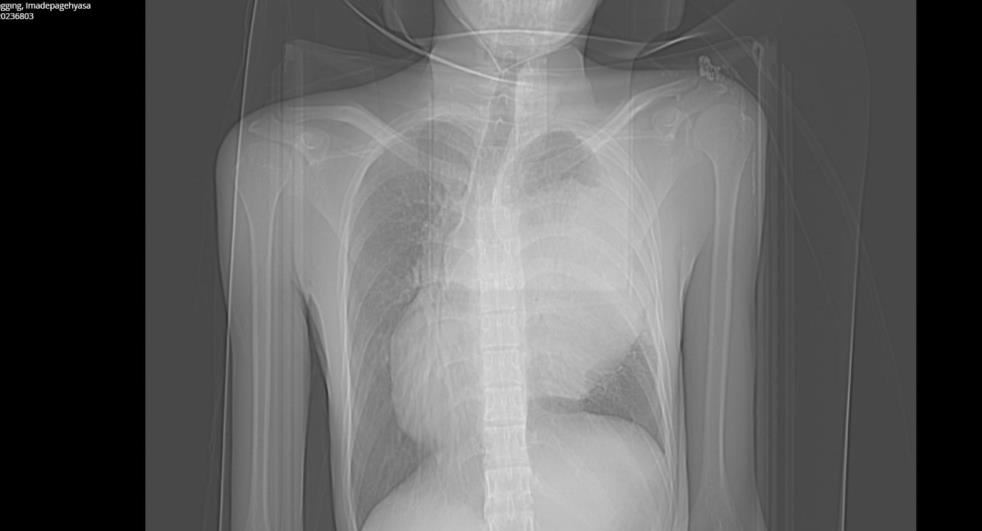

Tatil için Alanya’ya gelen 19 yaşındaki Endonozyalı I Made Pagehyasa Sanggıng, ağzından öksürükle birlikte kan gelmesi şikâyetleri ile Alanya Eğitim ve Araştırma Hastanesi Acil Servise başvurdu. Yapılan tetkik ve görüntülemeler neticesinde Sanggıng’ın sağ akciğerin tamamen fonksiyon dışı kalmasına yol açan bir kitle tespit edildi.

Kitlenin ayrıca kalbe ve diğer hayati organlara da ciddi bir baskı oluşturduğu belirlendi. 19 yaşındaki hasta ALKÜ Tıp Fakültesi Göğüs Cerrahisi Anabilim Dalı Başkanı Dr. Öğretim Üyesi Oktay Aslaner tarafından acil ameliyata alındı. Başarılı geçen operasyon sonunda hasta yeniden sağlığına kavuştu.

Hastanın yeniden sağlığına kavuştuğunu ifade eden Dr. Aslaner, “Acile başvuran Endonezyalı hastamızda tetkikleri sonucunda sağ göğüs kafesinin içinde dev bir kitle tespit edildi. Kalbi tamamen karşı tarafa itmiş, sol akciğerin ana atar damarını nerdeyse kapatmış şekildeydi.

Ekibimle birlikte ameliyata aldık. Ameliyatta sağ göğüs kafesinden iki akciğer arasında köken alan ve sol hemotoraksı dolduran 3 kilo ağırlığında bir kitle çıkardık. Sonrasında hastanın akciğeri açıldı, kalbi rahatladı, akciğer atar damarı normal hale geldi.